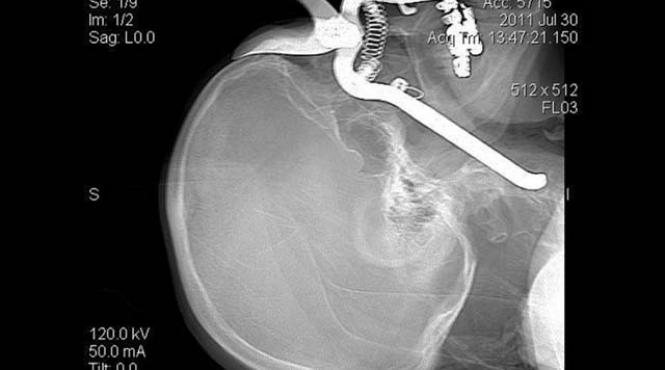

Bătrân sănătos după ce mânerul unei foarfece de grădinărit i-a străpuns capul, dinspre orbită până în carotidă